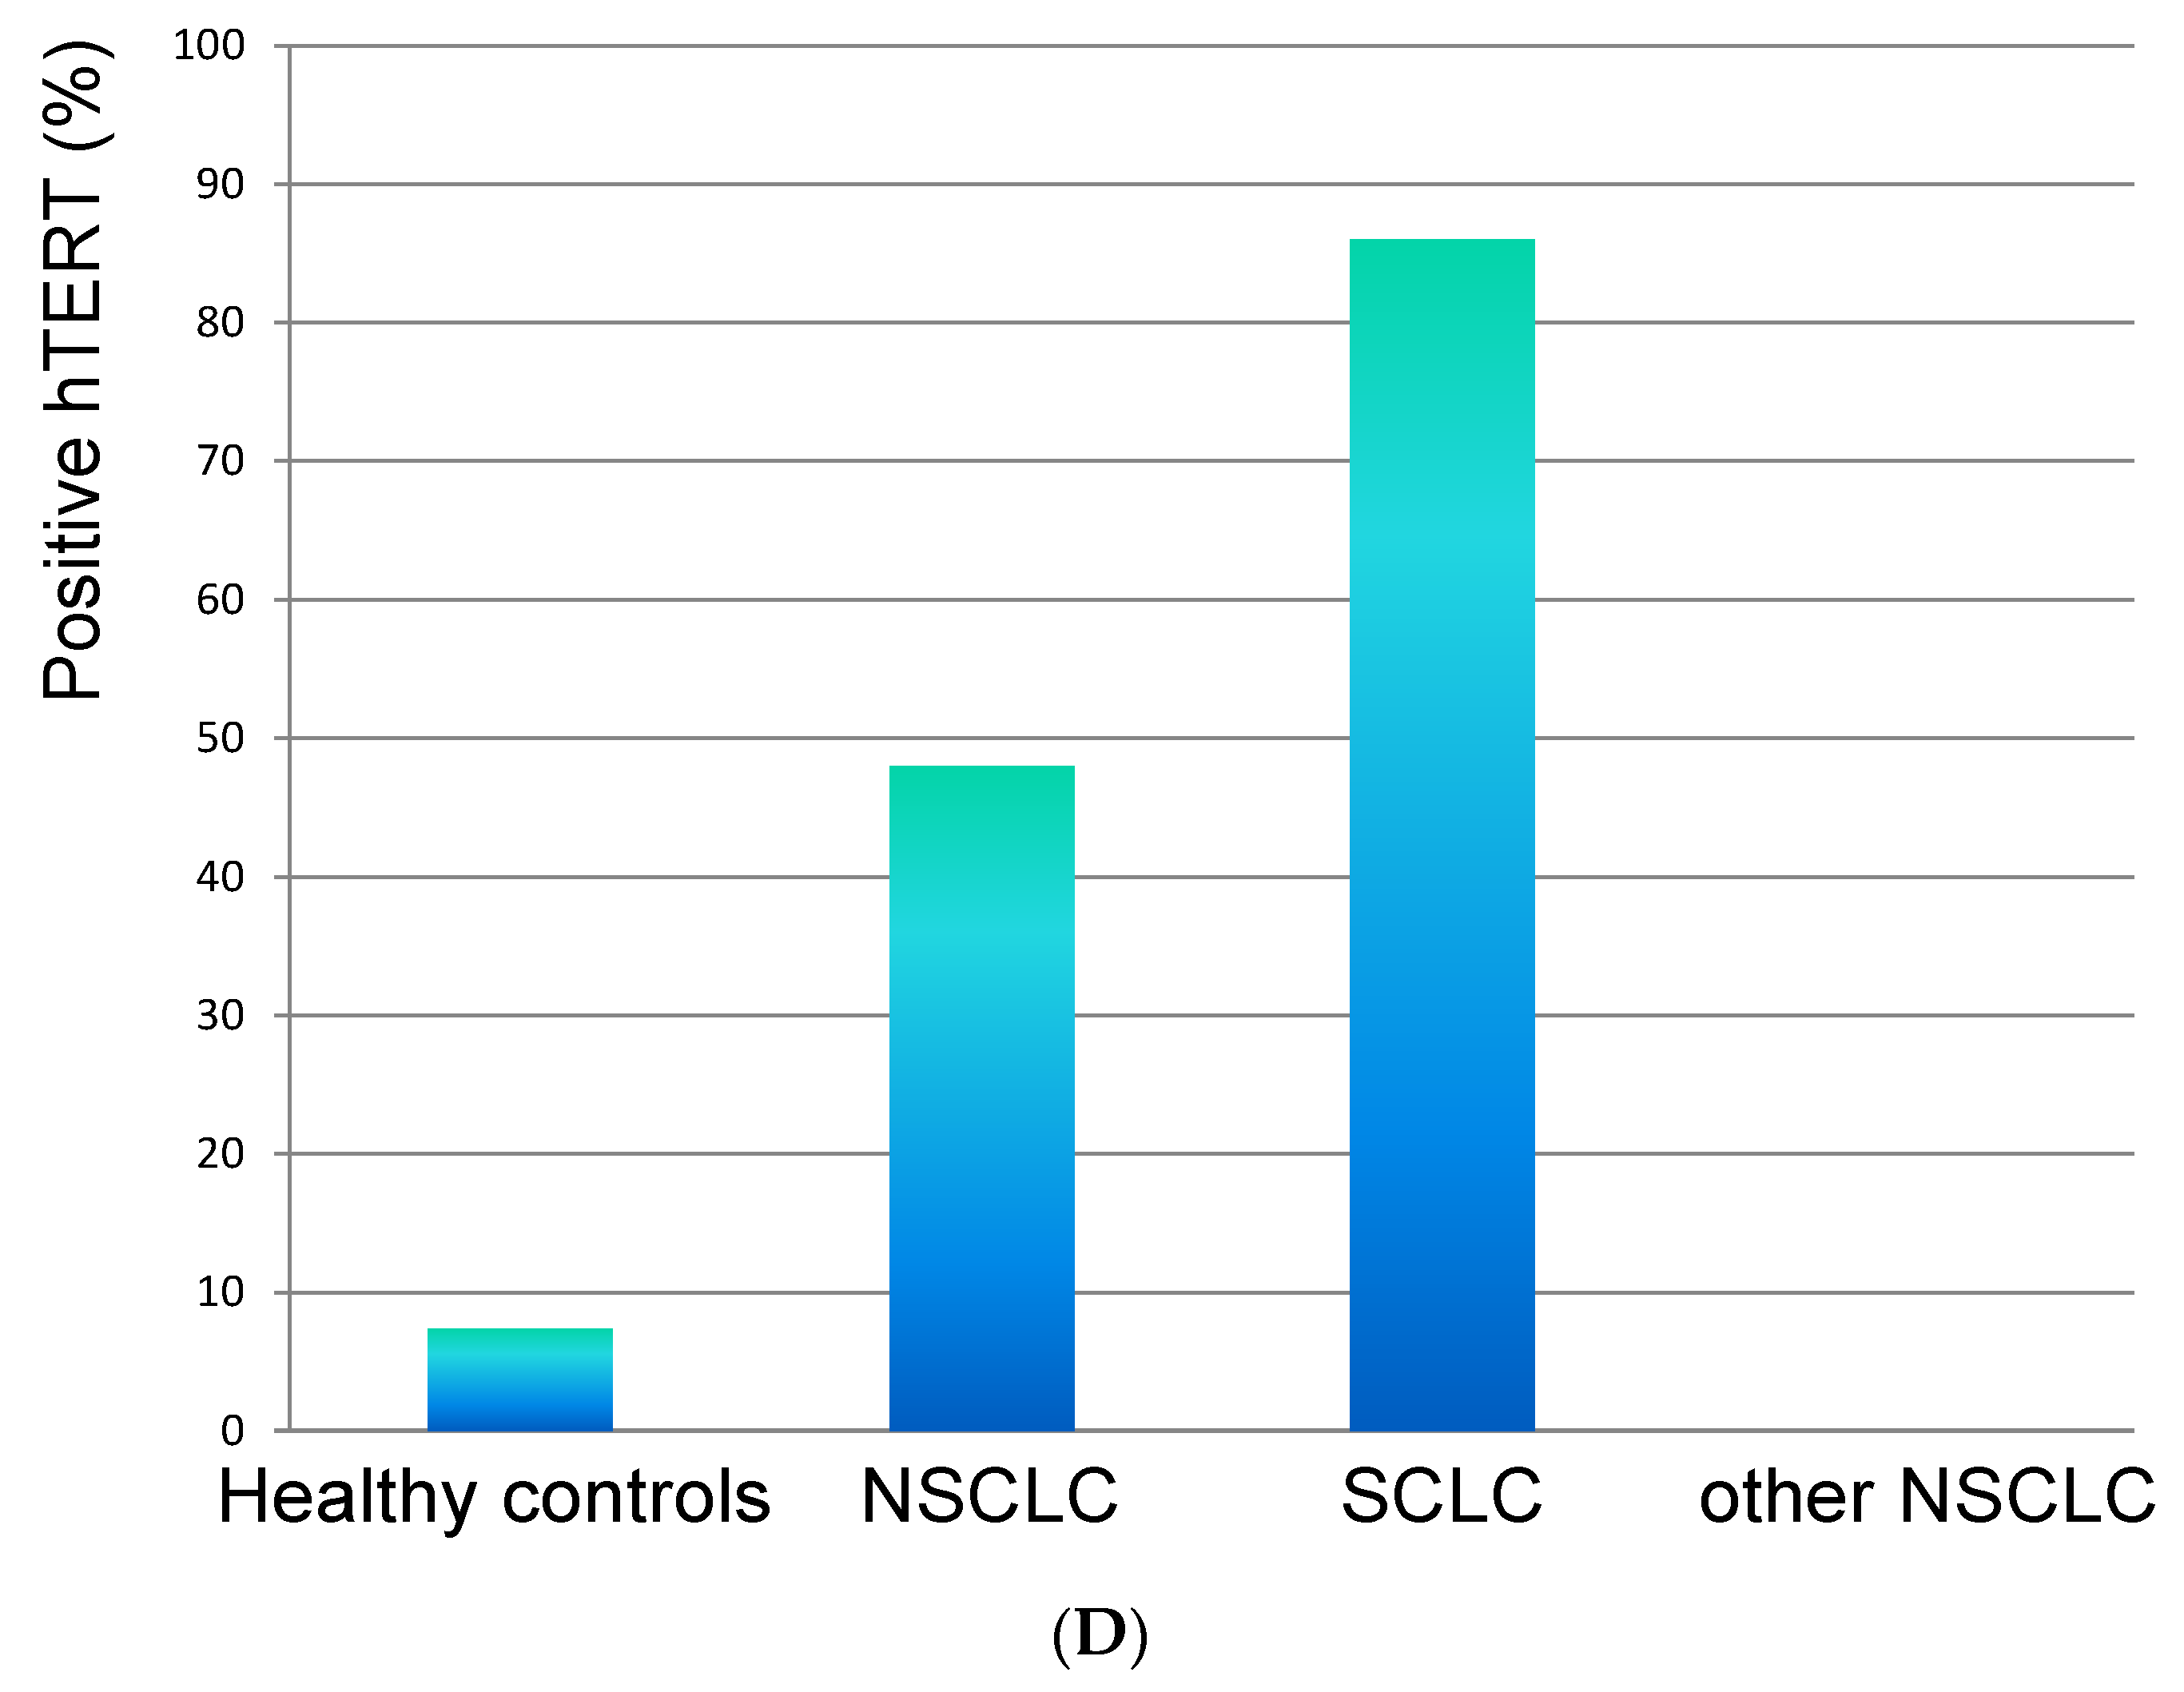

3.3. The Dynamics of hTERT at Time of Evaluation Regarding the Status of Metastasis